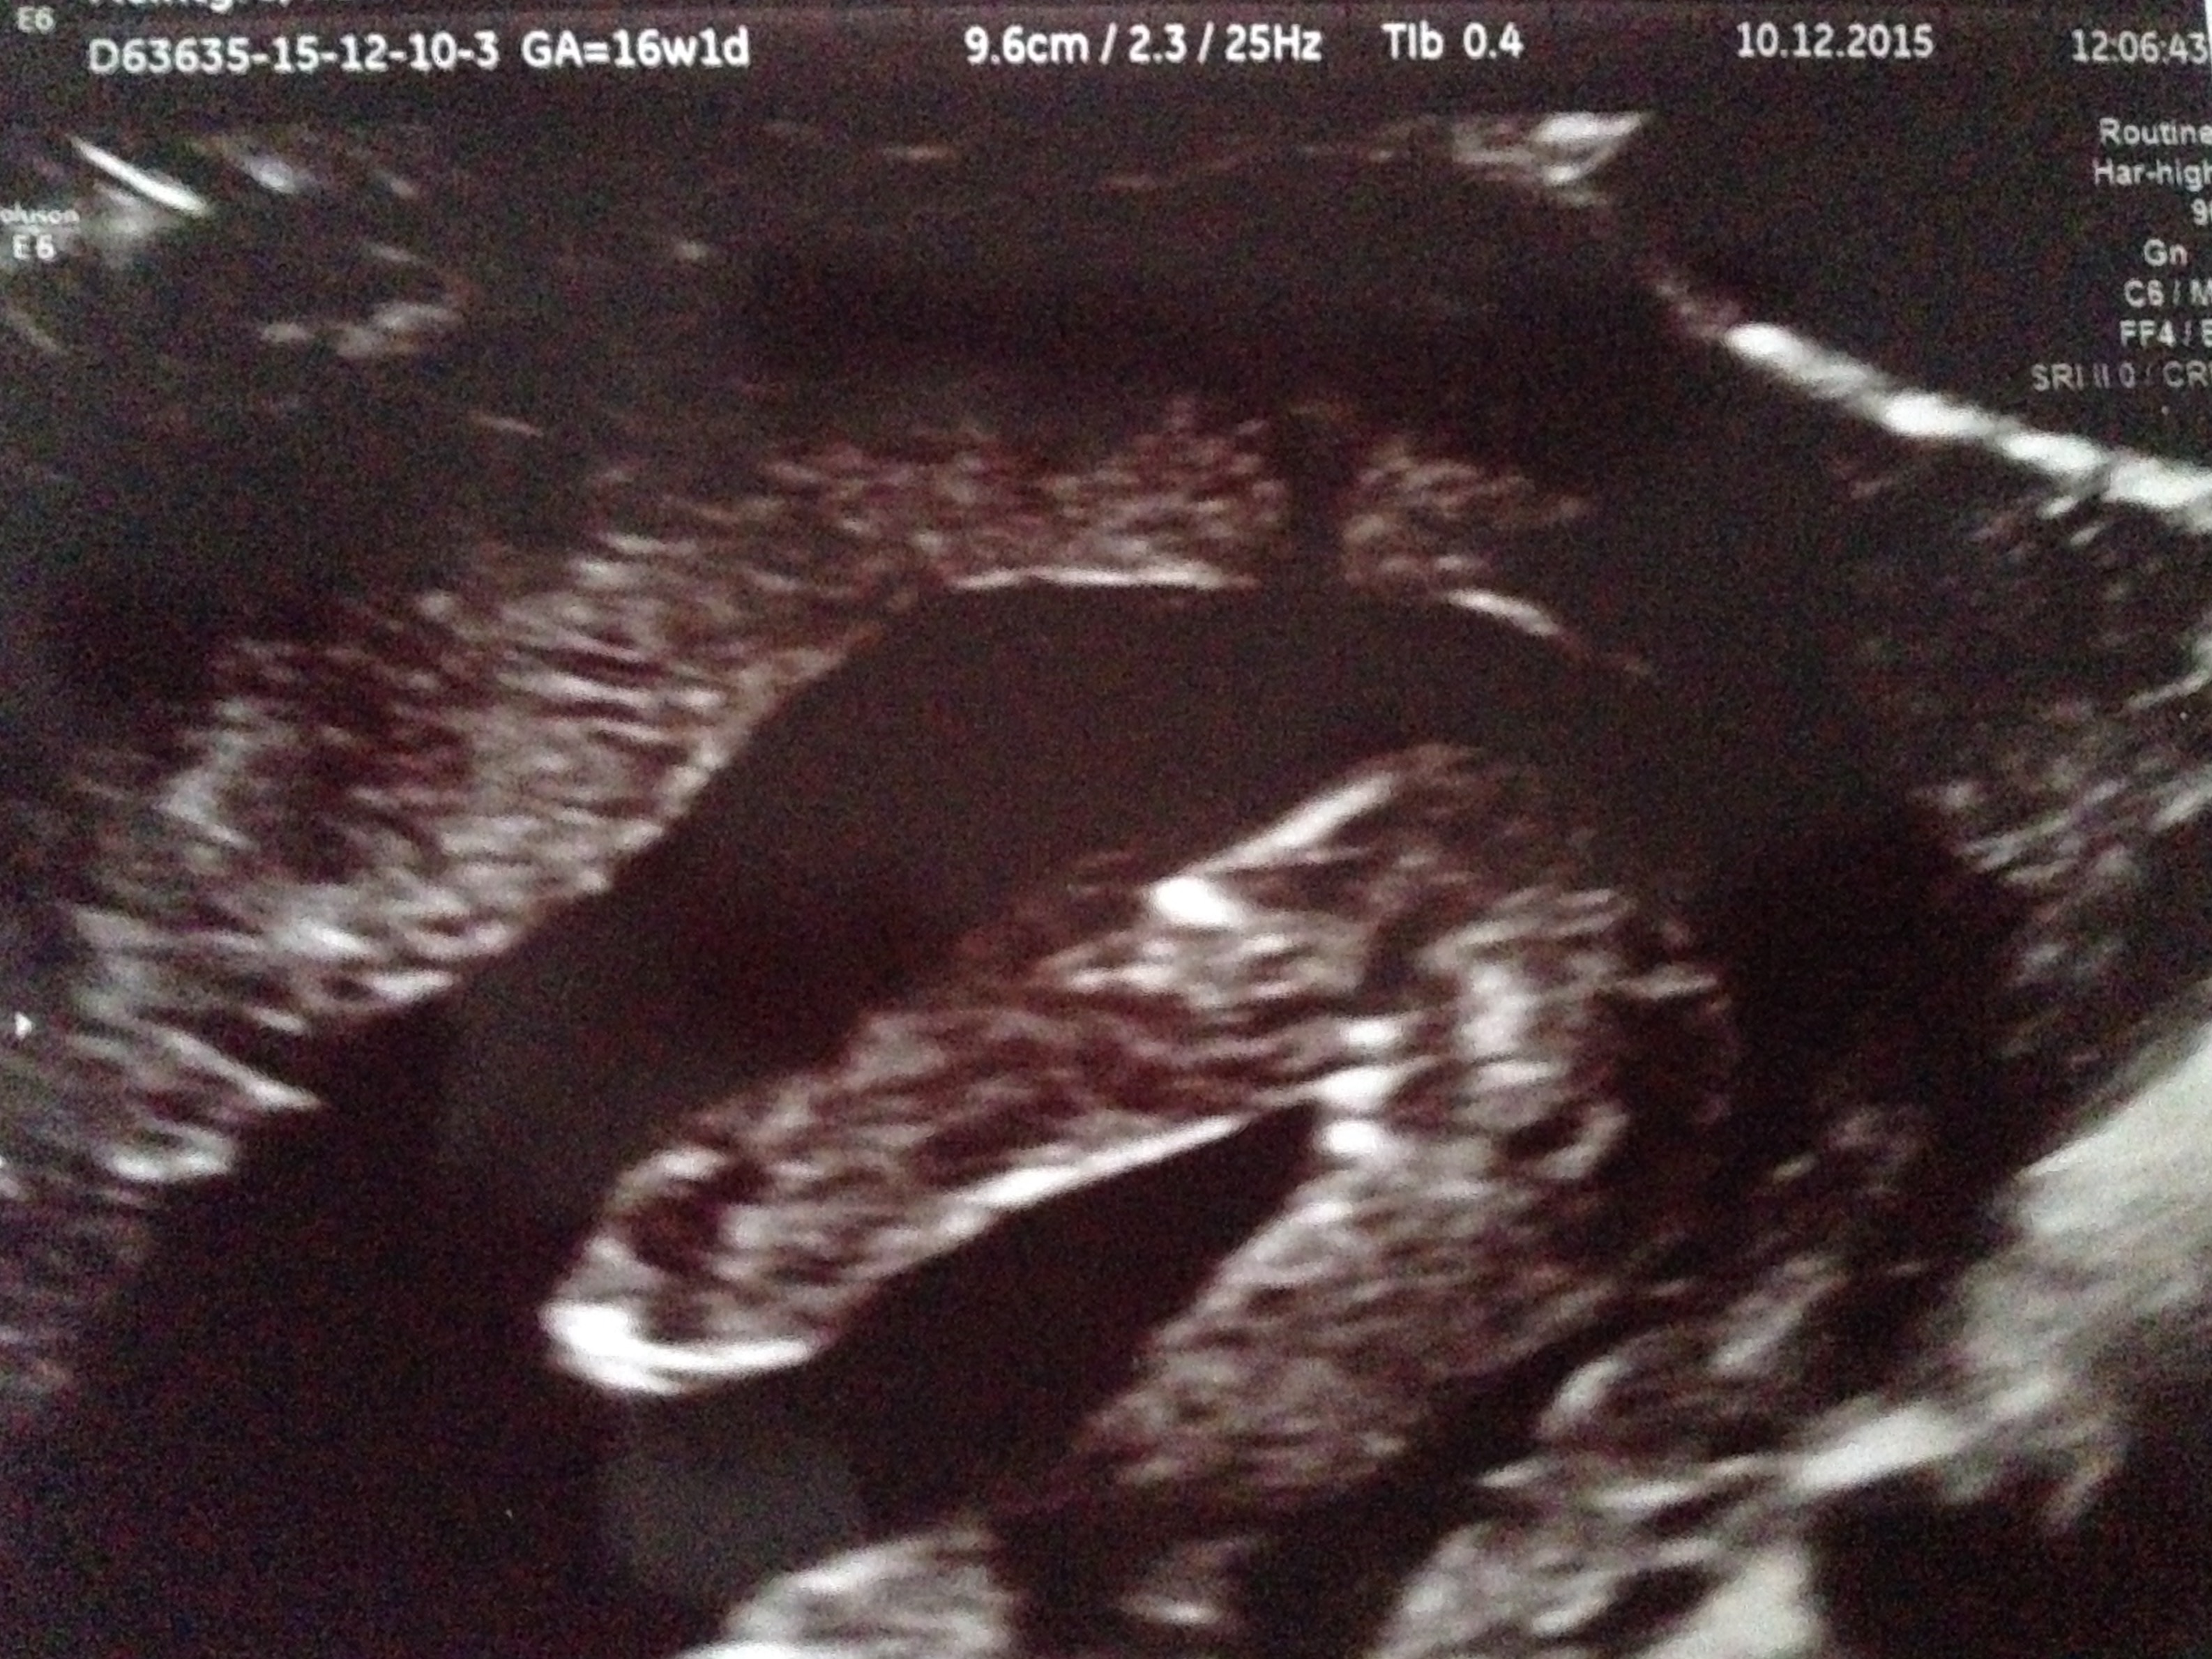

Just had my gender scan at 16weeks +1 but the lines are not straight between the legs like every other potty shot scan I've looked at. I was told girl because there are 3 white lines but it's not in the same place as all the other potty shots I've seen. What are these lines? Are they really girl parts or something else? Please help!!Attachment 28884